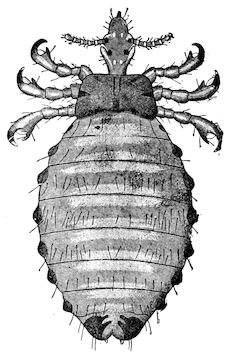

Fig. 1.—Rachitis in a young goat.